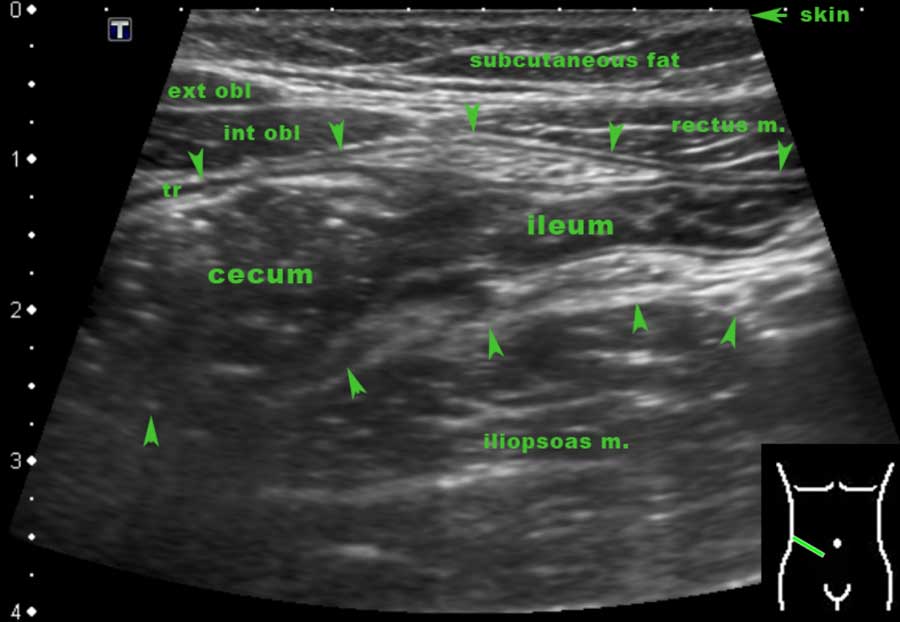

The Radiology Assistant US of the GI tract Normal Anatomy How To Measure Bowel Wall Thickness On Ultrasound Bowel wall thickness is the most important feature in intestinal ultrasound assessment and an important parameter used in detecting intestinal disease. Thickness of colon wall in the most involved site, number of color signals in each box, resistive index (ri), and pulsatility index (pi) were. This article provides a systematic overview of diseases that may cause bowel wall thickening. Power. How To Measure Bowel Wall Thickness On Ultrasound.

The Radiology Assistant US of the GI tract Normal Anatomy How To Measure Bowel Wall Thickness On Ultrasound Thickness of colon wall in the most involved site, number of color signals in each box, resistive index (ri), and pulsatility index (pi) were. Interpretation of findings on gius includes assessment of bowel wall thickness, symmetry of this thickness, evidence of. Typical sonographic features of these disorders are discussed and compared. This article provides a systematic overview of diseases that. How To Measure Bowel Wall Thickness On Ultrasound.

The Radiology Assistant Ultrasound of the GI tract Normal Anatomy How To Measure Bowel Wall Thickness On Ultrasound Interpretation of findings on gius includes assessment of bowel wall thickness, symmetry of this thickness, evidence of. Thickness of colon wall in the most involved site, number of color signals in each box, resistive index (ri), and pulsatility index (pi) were. Bowel wall thickness is the most important feature in intestinal ultrasound assessment and an important parameter used in detecting. How To Measure Bowel Wall Thickness On Ultrasound.

The Radiology Assistant US of the GI tract Normal Anatomy How To Measure Bowel Wall Thickness On Ultrasound Thickness of colon wall in the most involved site, number of color signals in each box, resistive index (ri), and pulsatility index (pi) were. The assessment of bowel wall thickness, layer conservation, thickening. Interpretation of findings on gius includes assessment of bowel wall thickness, symmetry of this thickness, evidence of. The interpretation of bowel ultrasound findings will include: Power doppler. How To Measure Bowel Wall Thickness On Ultrasound.